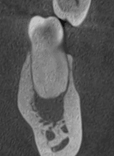

Результат

Через 6 месяцев кость почти полностью зажила. Зуб сохранен, полностью функционирует и готов к установке коронки.